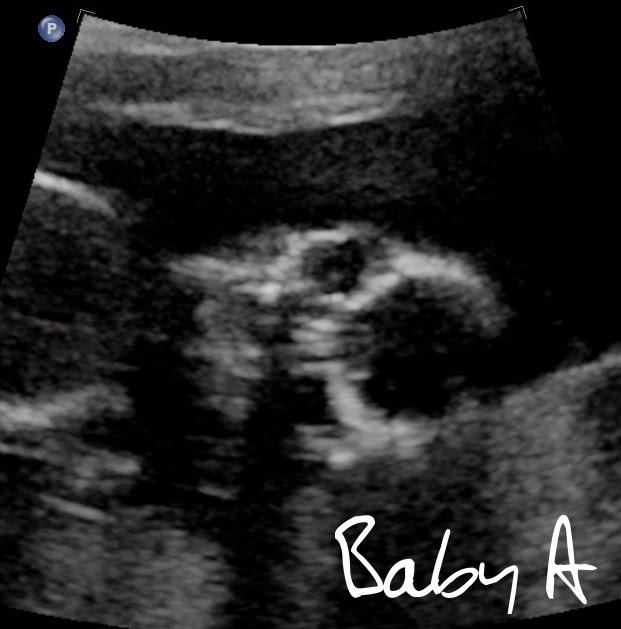

Otherwise, the babies both looked great. They did a very in depth scan: we saw all four chambers of their hearts, full stomachs, livers, brain parts, and all that good stuff. Both babies are measuring about a week ahead and weighing in at an estimated 4oz each. So that's great. Baby A was where I always find it with my doppler, and didn't really move from that spot during the scan. It rolled some and wiggled, but remained stationary. It's placenta is posterior, a bit to the right. Baby B was moving around all over, just like when I'm trying to find it with the doppler. It was everywhere, and very uncooperative (reminds me of how V was). The placenta was a little anterior and to the left.

Otherwise, the babies both looked great. They did a very in depth scan: we saw all four chambers of their hearts, full stomachs, livers, brain parts, and all that good stuff. Both babies are measuring about a week ahead and weighing in at an estimated 4oz each. So that's great. Baby A was where I always find it with my doppler, and didn't really move from that spot during the scan. It rolled some and wiggled, but remained stationary. It's placenta is posterior, a bit to the right. Baby B was moving around all over, just like when I'm trying to find it with the doppler. It was everywhere, and very uncooperative (reminds me of how V was). The placenta was a little anterior and to the left.My favorite bit of the scan was when she was measuring baby B's feet (or trying to) and it started kicking at baby A's feet, who in turn kicked back! And they proceeded to kick each other for a bit. It made me laugh, and it definitely made things a lot more real too.